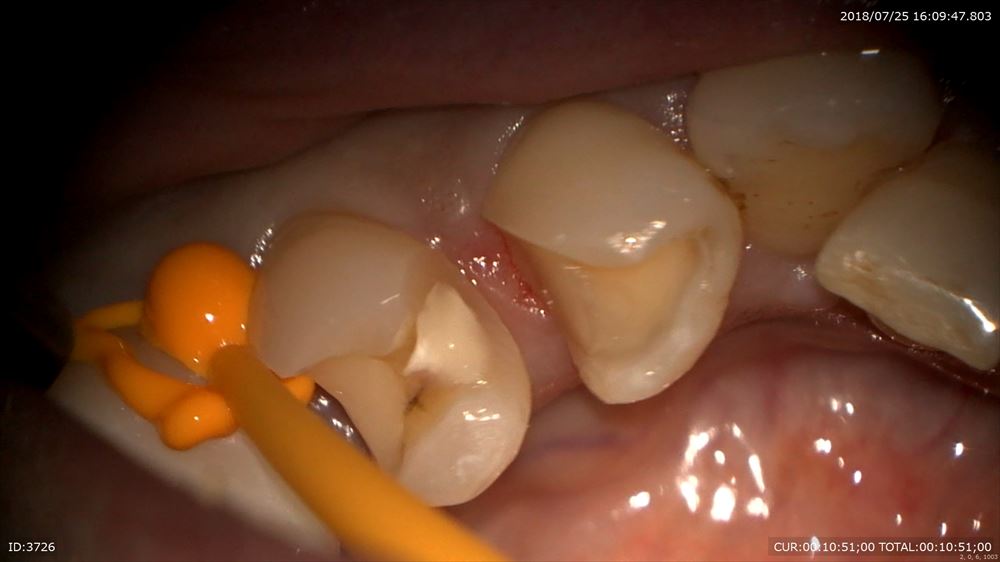

問題ないので精密な型とり。ここもマイクロスコープを使用。

活性材

シリコン

気泡をいれない

マイクロスコープを使用することでこのように形成もスムーズに歯茎を傷めず治療が可能です。